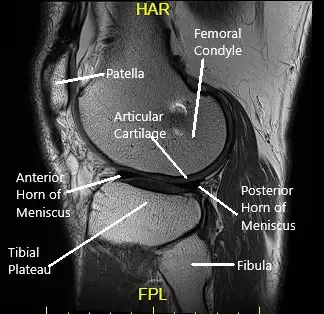

How the Body Part Normally Works? (Relevant Anatomy)

The knee joint is a hinge joint composed of the thigh bone (femur), shin bone (tibia), fibula, and kneecap (patella). The ligaments, cartilage, and menisci work together to provide stability and allow smooth movement.

- Articular cartilage cushions and protects the bones.

- Menisci serve as shock absorbers between the femur and tibia.

- Ligaments, including the ACL, PCL, MCL, and LCL, stabilize the knee by preventing excessive movement.

- Synovium produces synovial fluid, which lubricates the joint to ensure smooth motion.